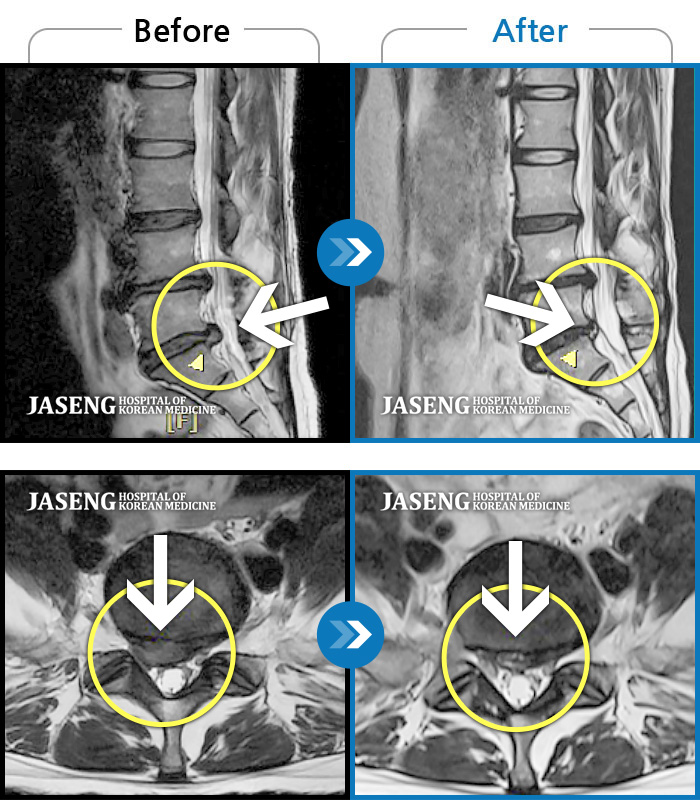

허리디스크

도움받은 사례

광주 · 장영우 원장

양측 허리부터 좌측 다리까지 이어지는 저림과 통증으로 걷기 힘들어 내원하였습니다.

촬영시기

2024.11.22 ~ 2025.05.16

2025.05.30